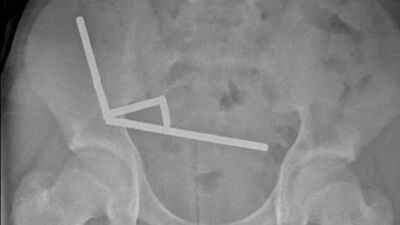

Röntgen görüntülerinde, çocuğun karnının sağ alt kısmında birbirine yapışmış metal yığınları tespit edildi ve çocuğun yaklaşık 100 mini neodyum mıknatıs yuttuğu belirlendi.